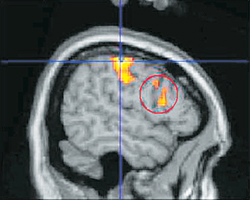

신체 부위를 암시한 광고를 볼 때의 뇌 반응을 촬영한 모습. 원으로 표시한 부분이 성적 흥분을 담당하는 뇌섬엽 영역이다. 실제로 성적으로 흥분했다는 것을 뜻한다. 사진 제공 고려대

소비자를 가장 적극적으로 몰입하게 만든 것은 은유적으로 신체 부위를 노출한 광고였다. 전두엽과 함께 성적 흥분을 담당하는 영역(뇌섬엽)이 활성화된 것이다. 다른 광고들에 비해 유일하게 실험 참가자들이 실제 성적 흥분을 경험한 경우다.